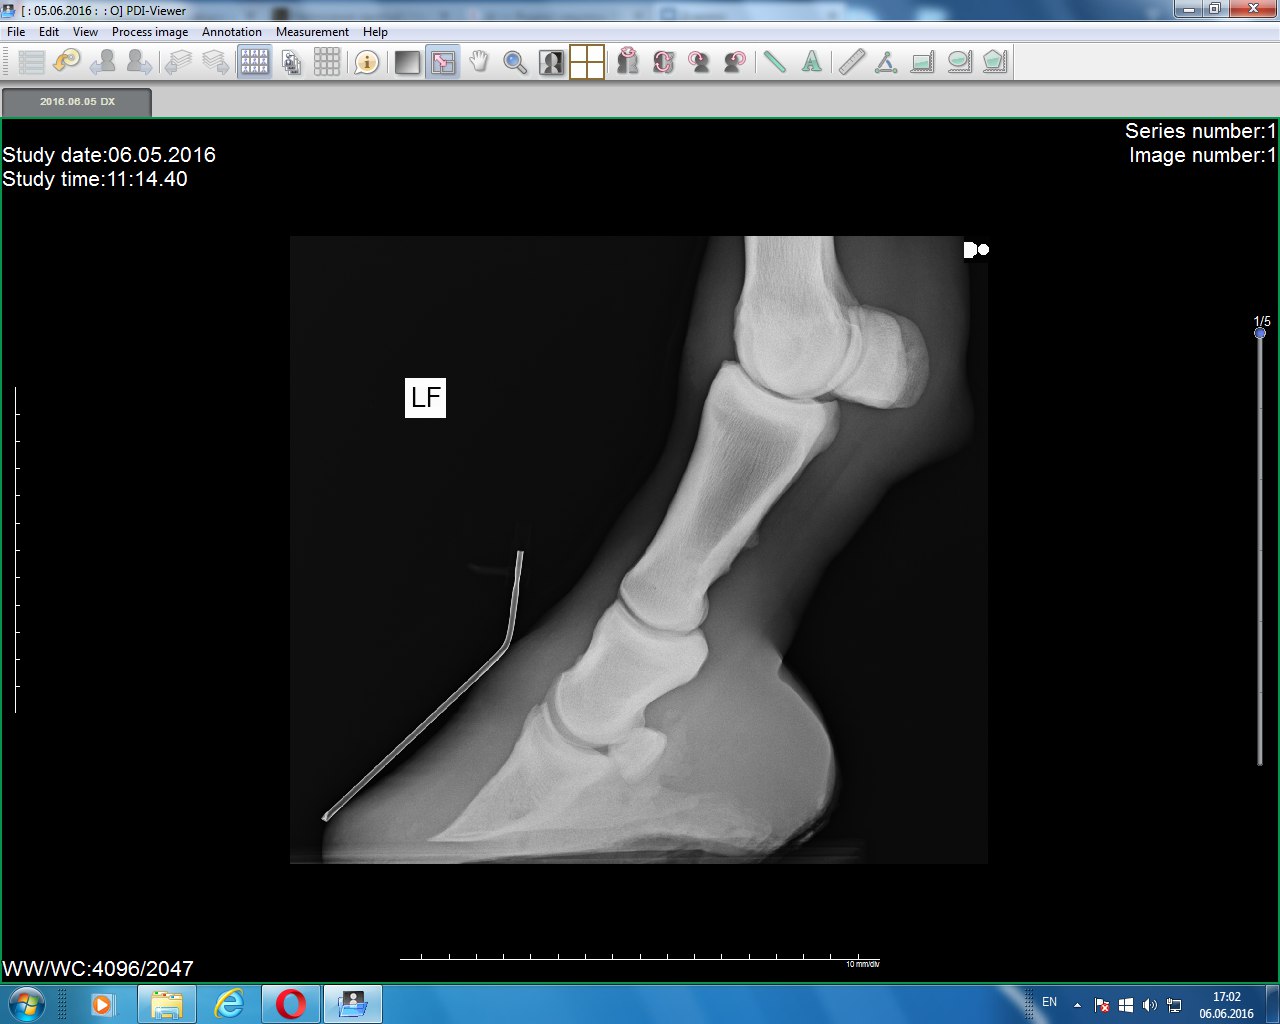

Левый перед (2014)

Левый перед(2015)

Левый перед(2016) Не обращайте внимание на обозначение, переснимали после правой ноги. и забыли изменить